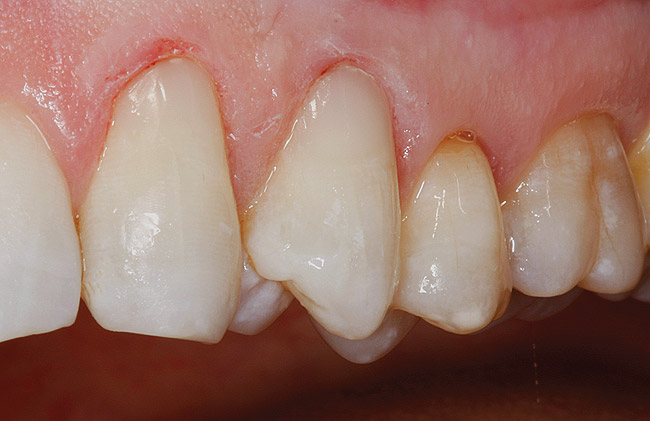

Figure  2  Loss of tooth surface surrounding amalgam and appearance of the restoration protruding from the tooth surface.

Figure 2

Characteristics of damage to tooth structures caused by acidity include wear on the occlusal surfaces of molars and a saucer shape on the cusps of molars (perimolysis).12 The erosion can vary from minor and subtle changes on the tooth surface, ie, loss of luster, a dull or matted look, to cupping on occlusal surfaces or incisal edges, which may extend to dentin. Usually, the erosive lesions demonstrate greater width than depth. When combined with abrasive forces or stresses, the tooth surface loss may occur at a faster rate (Figure 2, Figure 3, Figure 4 and Figure 5).